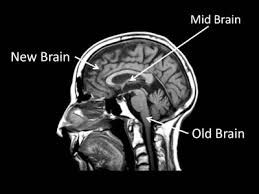

brain and nerve system